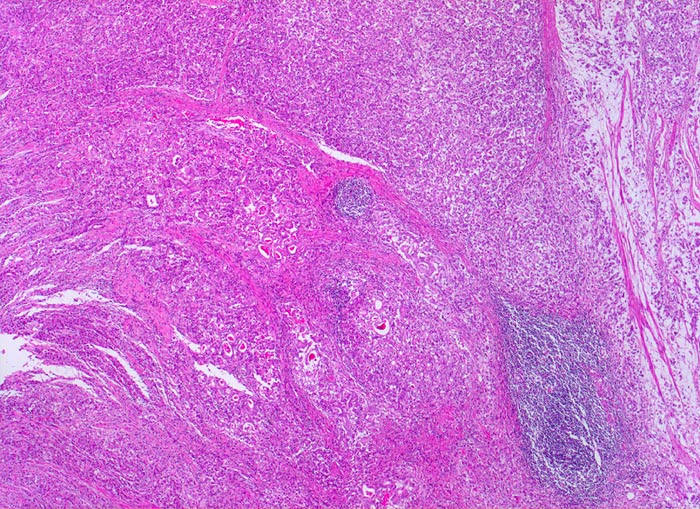

Beim diffusen Typ nach Lauren infiltrieren Einzelzellen oder Zellstränge, meist mit Siegelringzellanteilen diffus die Magenwand. Eine Drüsenbildung ist nicht erkennbar. Dieser Tumortyp tritt bei relativ jungen Patienten auf und ist mit genetischen Faktoren assoziiert (positive Familienanamnese). Wegen des diffus infiltrativen Wachstums ohne makroskopisch sicher erkennbare Grenze müssen diese Tumoren mit einem grösseren Sicherheitsabstand operiert werden. Siegelringkarzinome machen rund 20% aller Magenkarzinome aus.

• Ein Grossteil des Tumorinfiltrats besteht aus einzeln oder in kleinen Gruppen liegenden Zellen mit intrazytoplasmatischen Schleimvakuolen, die teilweise den Kern verdrängen (Siegelringzellen): diffuser Typ des Magenkarzinoms nach Lauren.

• Lymphgefässeinbrüche.